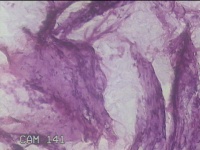

右侧输卵管系膜囊肿

大体所见

灰白粉红色囊性肿物0.7x0.5x0.3cm一个,表面光滑,切开肿物,内见大量清亮液体,囊壁厚0.1cm。